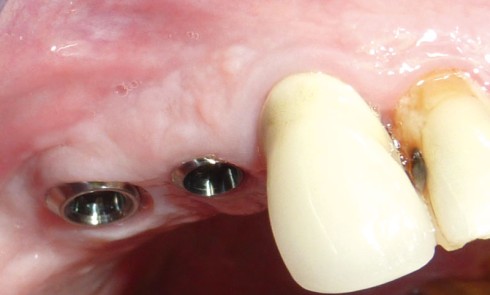

Article réservé à nos abonnés Intérêt des implants à col transgingival long dans les situations de profil de crête inclinée

Rappel sur la cicatrisation des tissus mous autour des implants en un temps Pendant la cicatrisation des tissus mous (4...